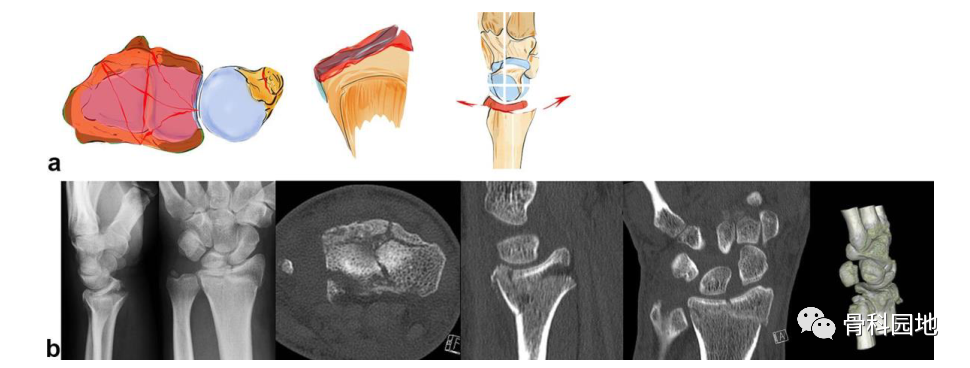

2、掌侧关节骨块

注:可以是大的或较小的边缘碎片。可能发生掌侧脱位,而背侧韧带保持完整 (a)。掌侧骨块:重要的尺桡韧带和尺腕韧带的起源 (b)。向掌侧脱位(c)。掌侧骨折从尺侧延伸到桡侧(d)。在 X 光平片上很容易忽略小的掌侧尺骨骨块,但轴位 CT 扫描容易显示该骨块 (e)